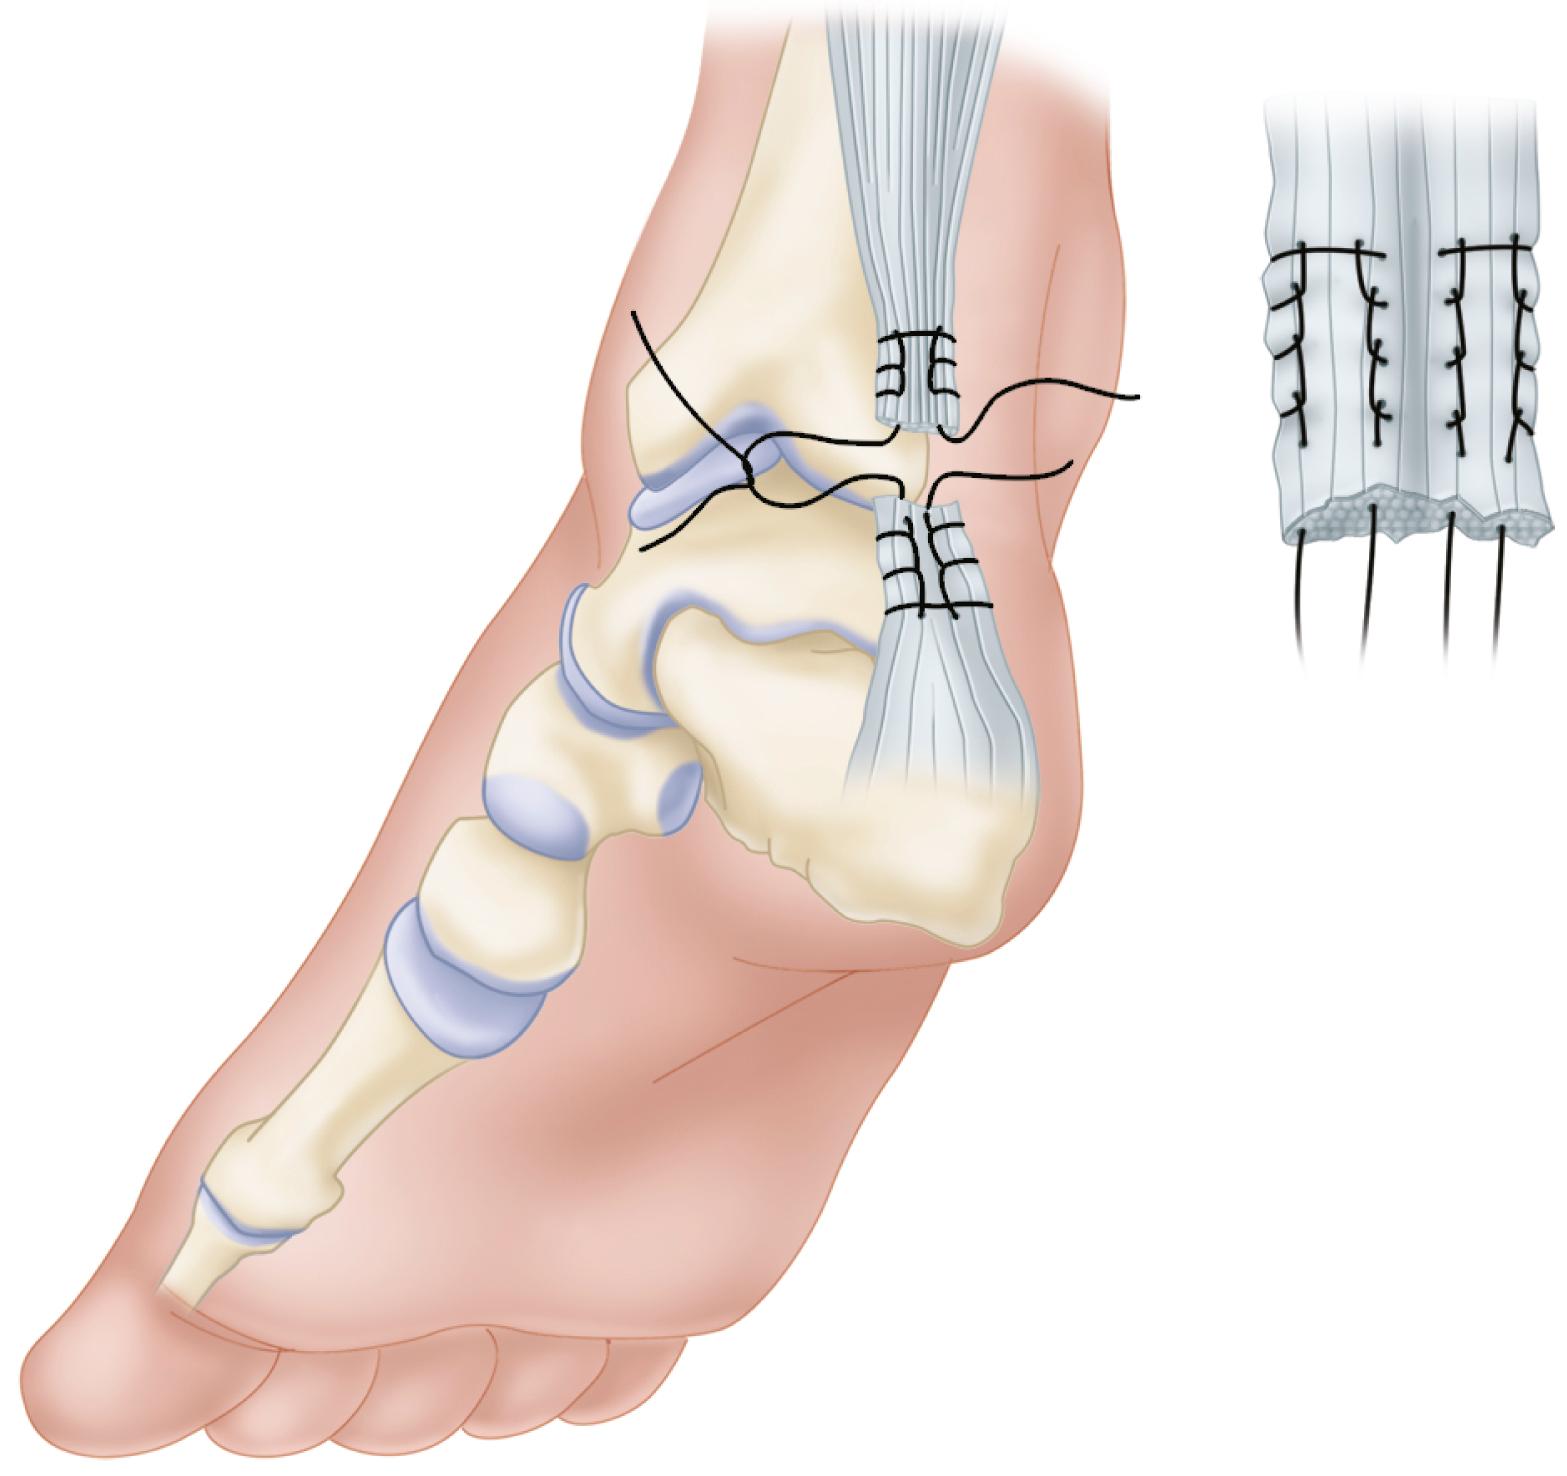

• Detach the peroneus brevis tendon from its insertion through a small incision at the base of the fifth metatarsal.

• Excise the aponeurotic septum, separating the lateral and posterior compartments, and deliver the freed peroneus brevis into the first incision.

• Dissect the tuberosity of the calcaneus and drill a hole large enough for passage of the tendon through the transverse diameter of the bone.

• Pass the peroneus brevis tendon through this hole and back proximally beside the Achilles tendon, reinforcing the site of rupture, and suture it to the peroneus brevis itself, producing a dynamic loop ( Fig. 48.19 ).

FIGURE 48.19, Dynamic loop suture of peroneus brevis to itself when end-to-end suture is not possible. SEE TECHNIQUE 48.11 .

Turco and Spinella described a modification in which the peroneus brevis is passed through a midcoronal slit in the distal stump of the Achilles tendon. The graft is sutured medially and laterally to the stump and proximally to the tendon with multiple interrupted sutures to prevent splitting of the distal tendon stump ( Fig. 48.20 ). This modification can be beneficial if a long distal stump is present.

FIGURE 48.20, Turco and Spinella modification. Peroneus brevis is passed through midcoronal slit in distal stump of Achilles tendon and sutured to stump and to tendon. SEE TECHNIQUE 48.11 .